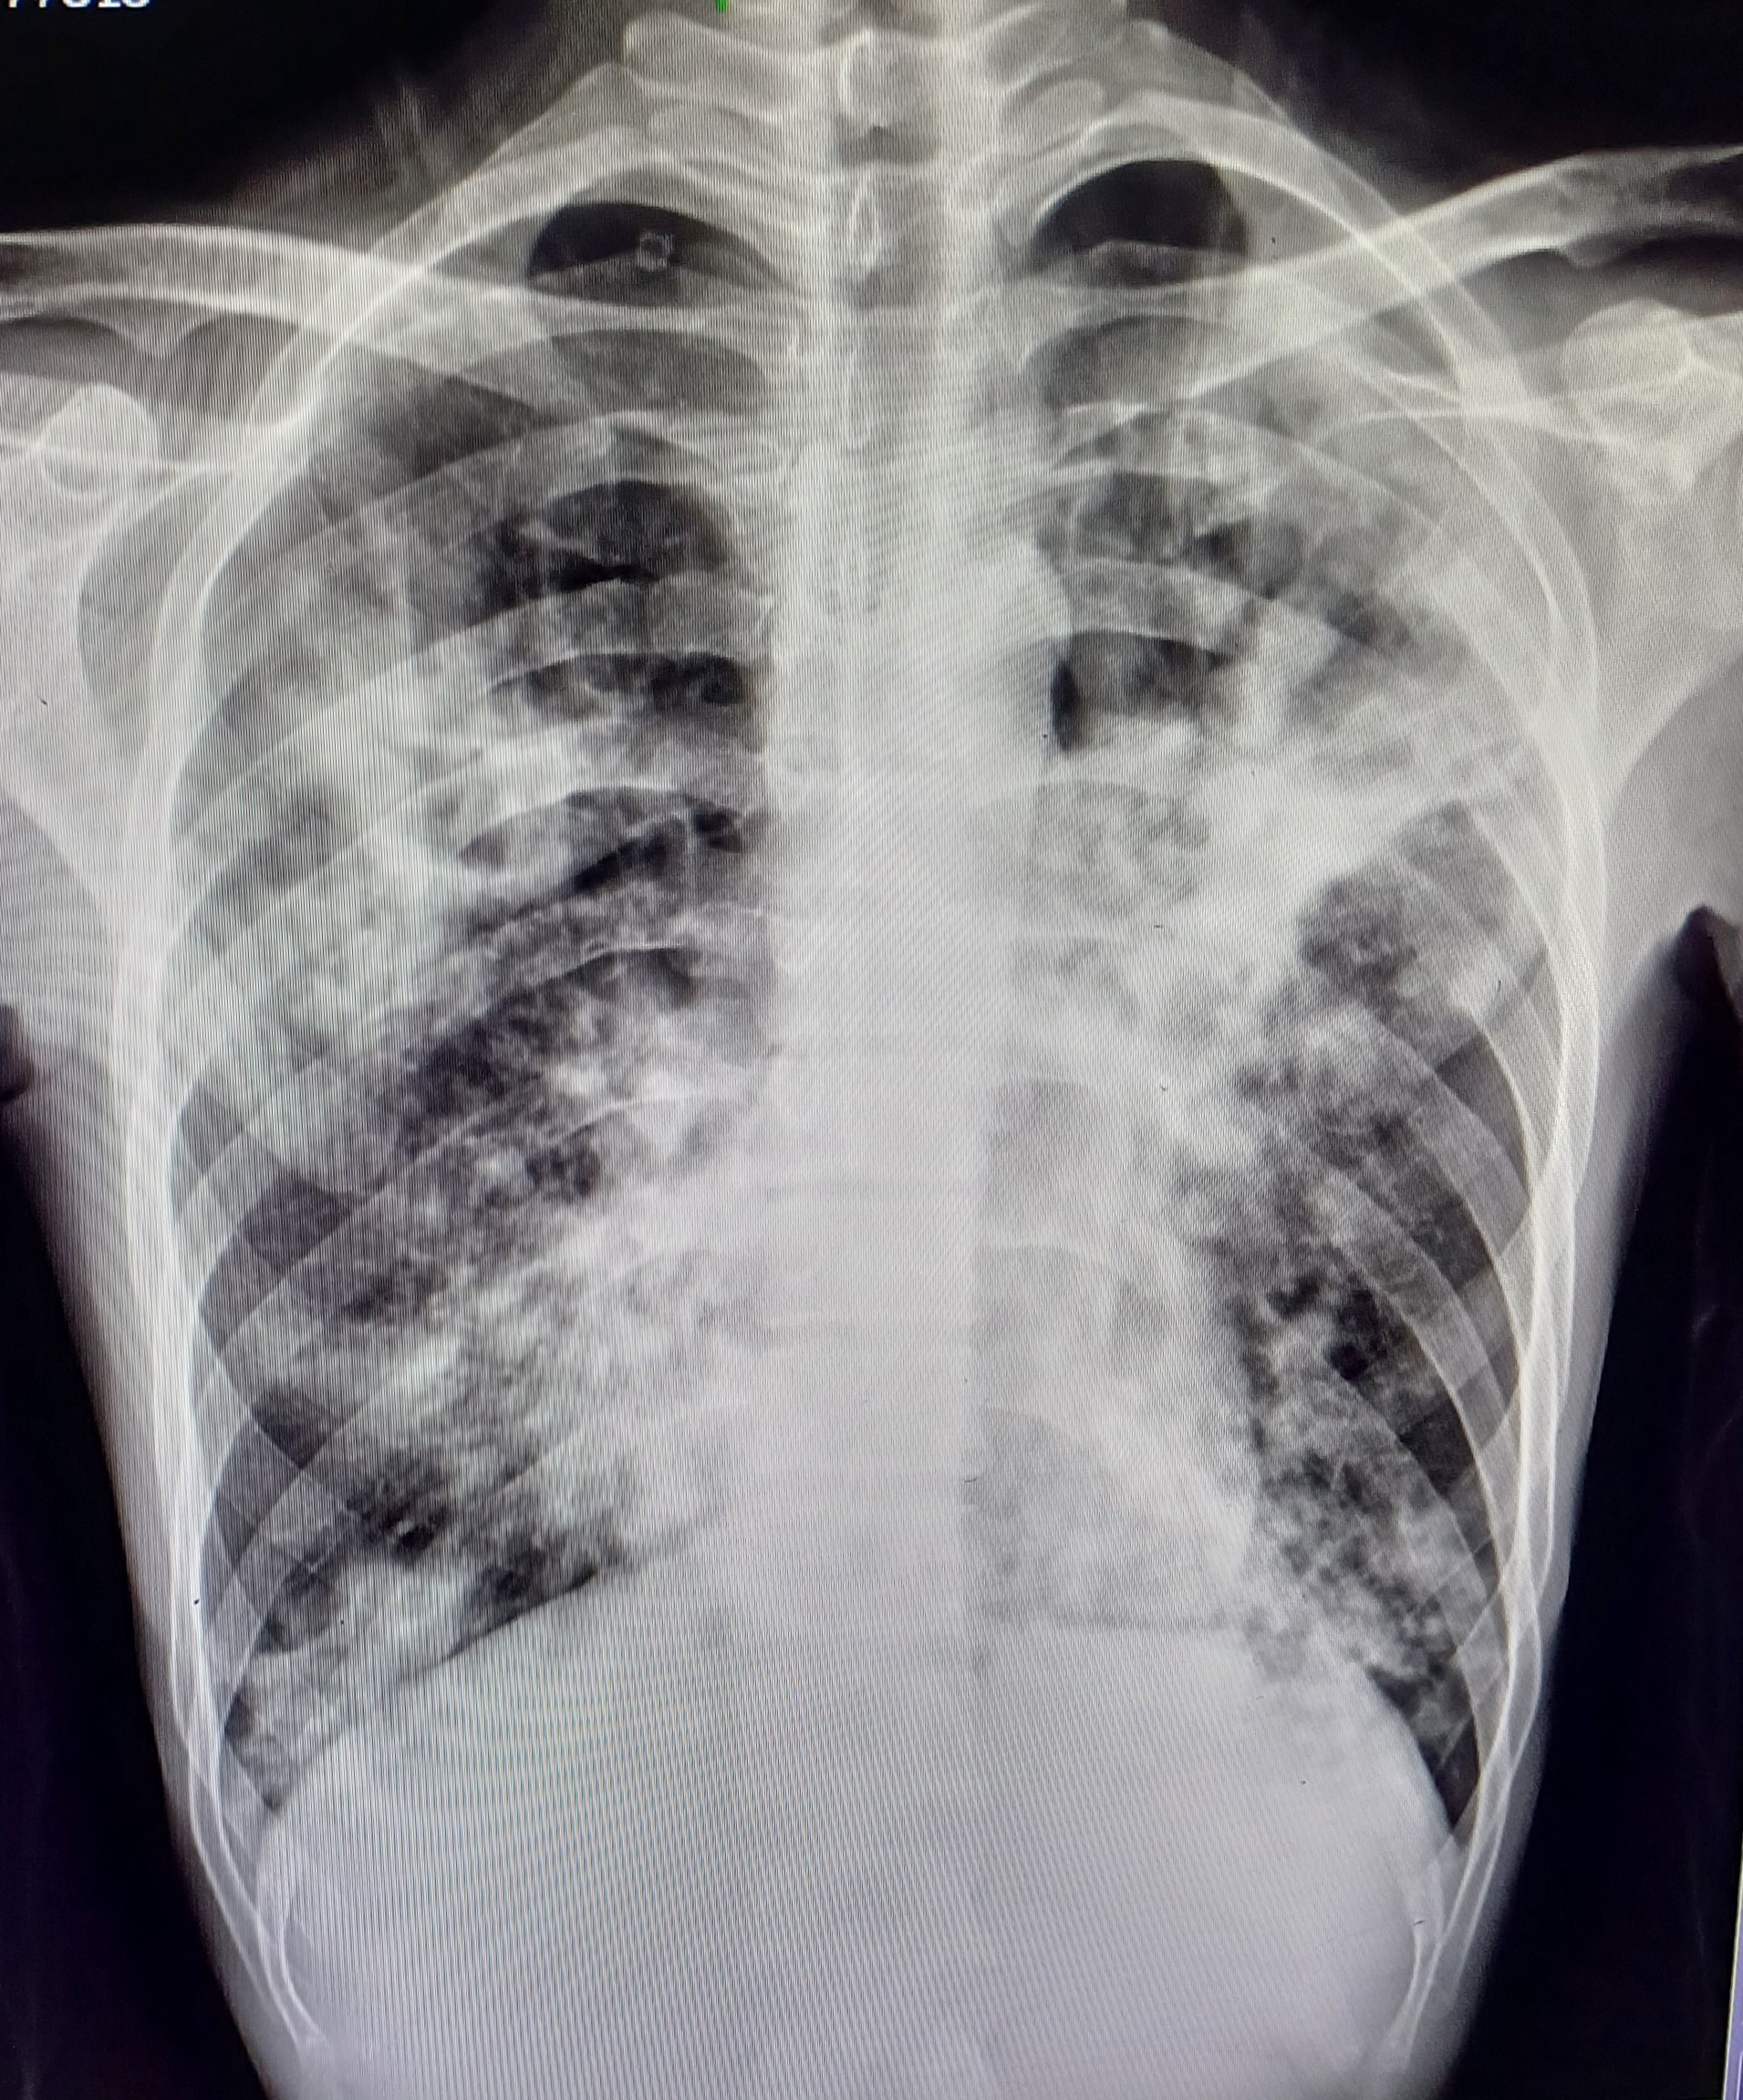

| 21 | IGGMC, Nagpur, Nagpur | P2 | 29-4451 | Vivek Sahu | Consent taken on Paper | 18 Yrs. |

Provisional Diag : Pulmonary Tuberculosis

Final Diag : Pulmonary Tuberculosis (Microbiologically Confirmed PTB) |

TB Case (Confirmed) | Fibro-cavitary lesion in the right upper zone, a cavity in the right mid zone and infiltration in the left mid zone | Abnormality visible on x-ray |

View |

|||